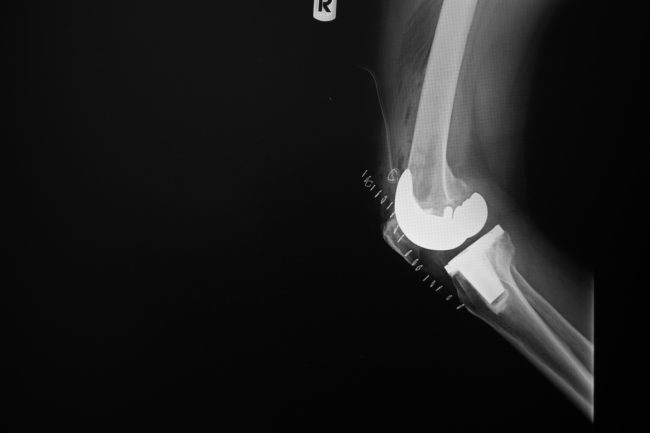

Artritis, artrosis y lumbago son las patologías reumatológicas más frecuentes en Canarias. ¿Sabías que hay más de 200 enfermedades reumatológicas?

Las enfermedades reumatológicas afectan a uno de cada cuatro adultos en España. Son la segunda causa de consulta, tras las infecciones respiratorias agudas, en Atención Primaria y la primera causa de incapacidad. Además, las enfermedades del aparato locomotor son las que más deterioran la calidad de vida de las personas por encima de las enfermedades…